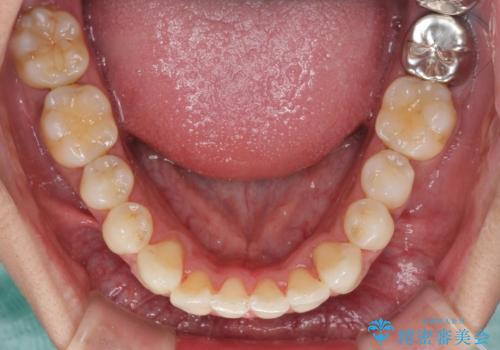

- 上下前歯の叢生を気にして来院された患者様です。

奥歯はクロスバイトとなっているので上顎は側方拡大を行いつつ、上下全体の叢生をインビザラインにより改善することとしました。

治療途中でクリーニングやホワイトニングを行い、歯列が整うと同時に明るい口元となりました。